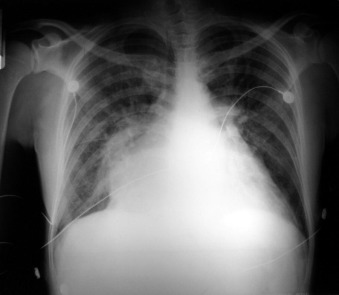

The radiographic findings of mitral stenosis ( Graphic 15-1 ; Figs. 15-1 to 15-16 ) reflect the pressure overload of the left atrium and pulmonary veins, and later of the right heart. As well, the commonly associated chronic atrial fibrillation contributes to (bi)atrial dilation. Associated rheumatic valvular lesions such as mitral regurgitation, tricuspid regurgitation, aortic insufficiency, and aortic stenosis/aortic insufficiency are common, and they alter the appearance of the heart.